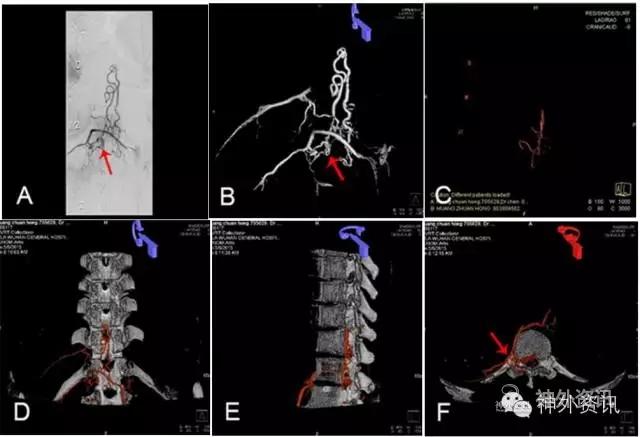

图3: 胸段硬脊膜动静脉瘘(SDAVF),↑示瘘口。A. 2D-DSA;B、C. 3D-DSA;D~F. 双容积重建冠状位、矢状位与轴位融合影像。

图3: G. 动态双容积重建冠状位融合影像。

图3: H. 动态双容积重建矢状位融合影像。

图3: I. 动态双容积重建轴位融合影像。

图3: J、K. 最大密度投影(MIP)冠状位、矢状位融合影像,可了解瘘与脊椎骨的上下左右前后的解剖关系。

图3: L. 动态旋转MIP。